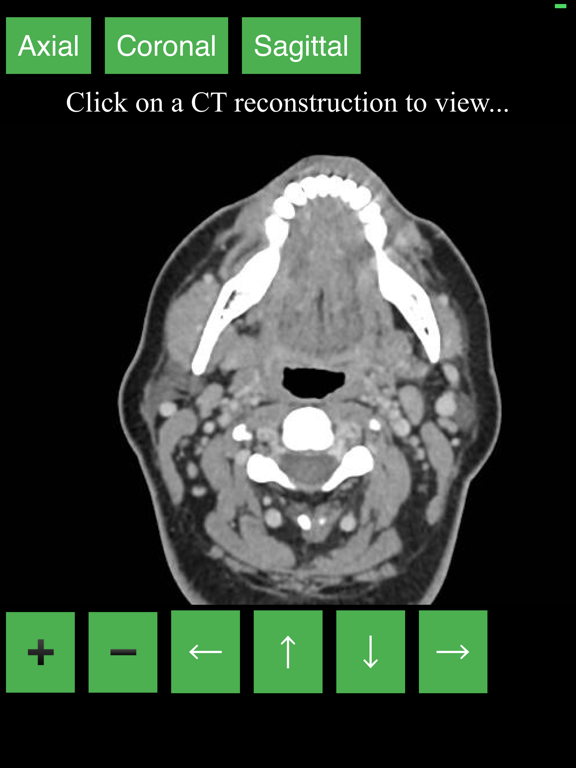

CT Neck

Lieu Duong

Radiology CT Viewer

Lieu Duong

Anatomy on Radiology CT

Lieu Duong

| 1 | CT Neck | 1.00 | 2.0 ⭐ |

| 2 | Radiology CT Viewer | 14 | 3.7 ⭐ |

| 4 | Anatomy on Radiology CT | 27 | 3.0 ⭐ |